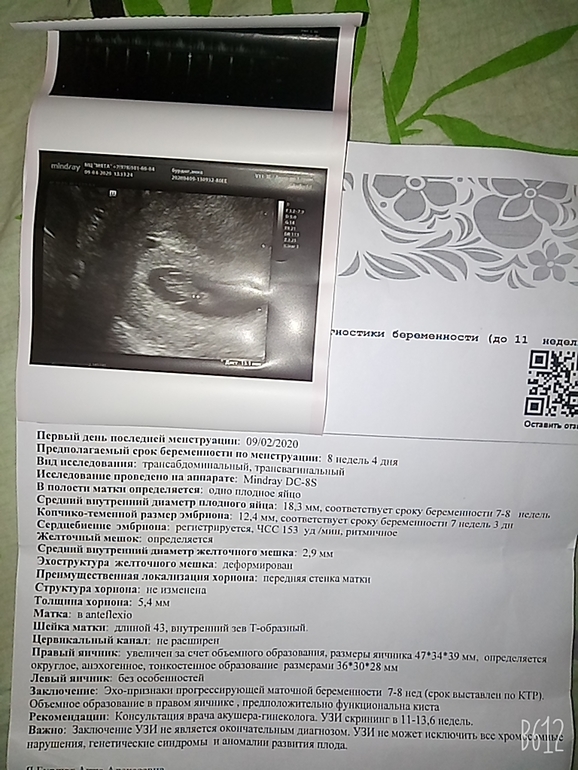

Узи,фото,Маленький желточный мешок(

Беременность- 1 триместр ( только до 10 недель)Здравствуйте,нужен совет.Понимаю что подобные вещи с врачем обсуждают но с карантином не так просто.Вчера была на платном узи.так как 24.03 была для того чтоб исключить невматочную,эмбрион не визуализировался.Волновалась,и решил еще раз пойти на УЗИ послушать сердечко.Ходила в платную там конечно слишком навязывают свои услуги,много того что просто мне не интересно.Перед Узи Сразу спрасили почему не пошла к врачу,ответила:в ЖК постоянно переносят запись из-за карантина,Выслушала что нельзя желеть денег нужно идти а вдруг мне поддержка нужна. Делая Узи врач охала-ахала мол слишком мал желточный мешок,малыш голодает.Срочно беги записывайся у них.Я то записалась, но не у них,явное давление.Да много внимание уделила это в посте,но впечатление именно такие.Теперь вопрос действительно ли так все плохо??Мама сказала успакойся,лучше фруктов купи,раньше так по узи не бегала и все у меня хорошо было.Девочки не стесняйтесь высказывайте свое мнение,мне важна адекватная оценка ситуации.Качество фото так себе